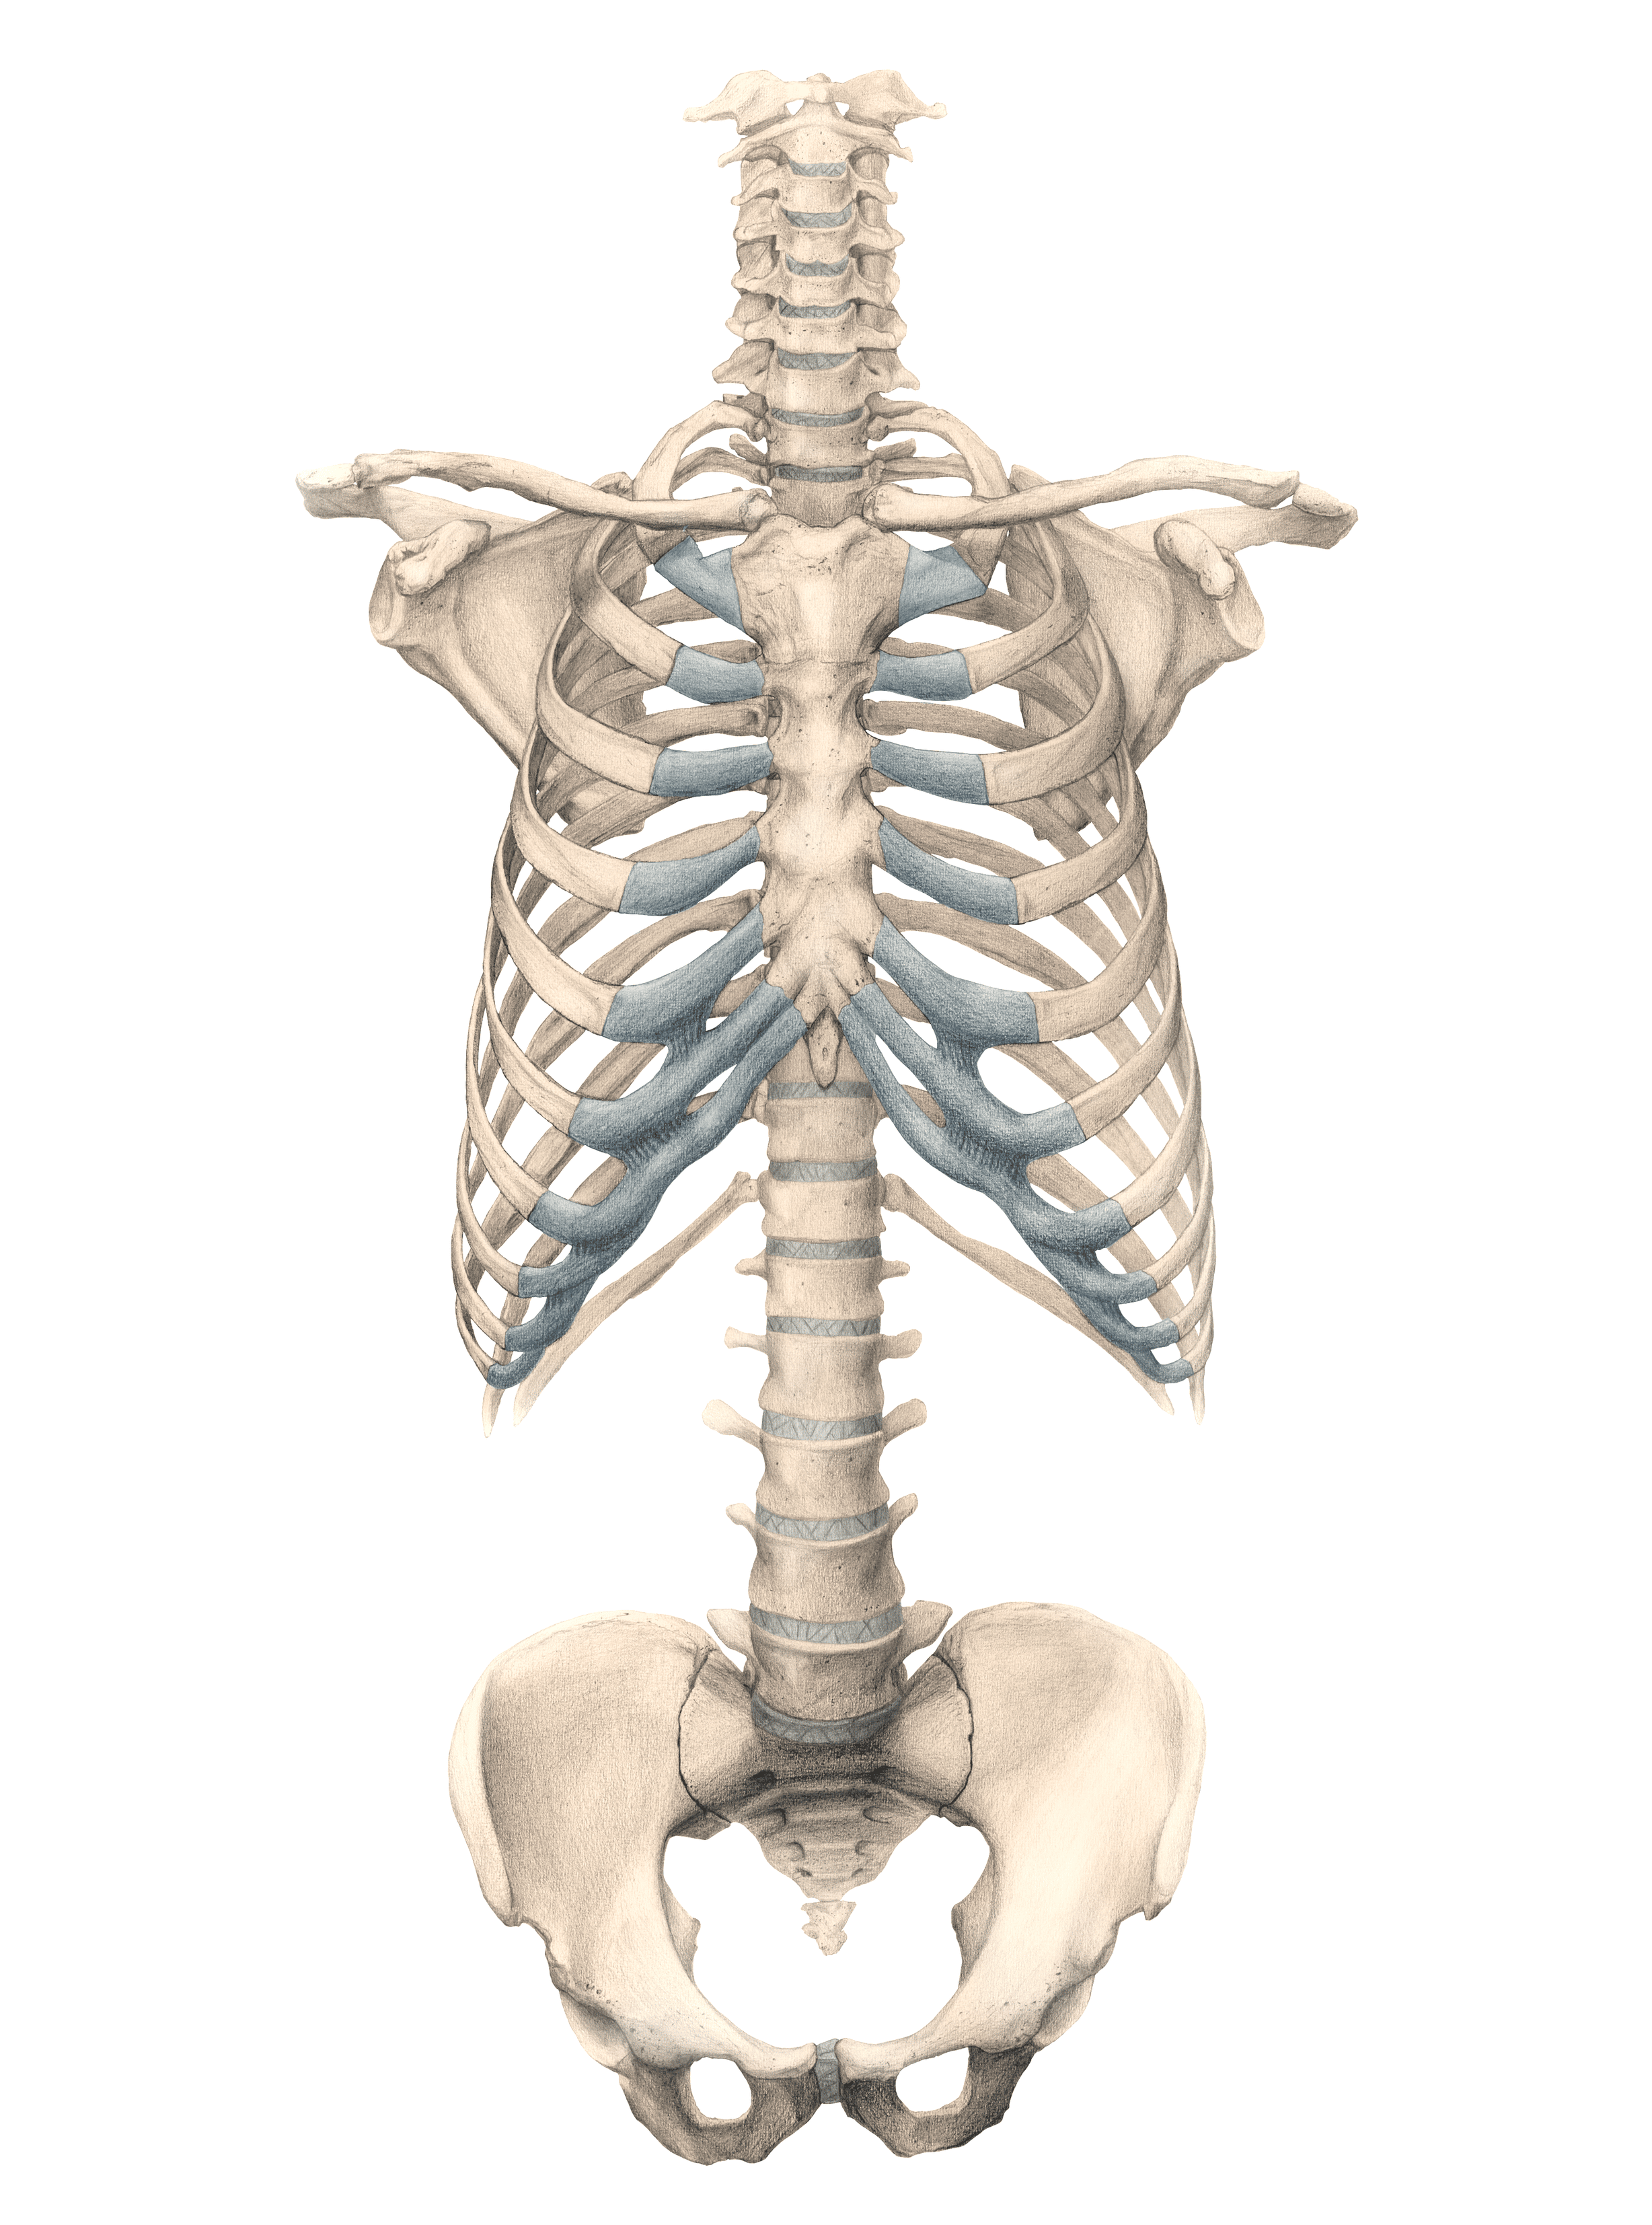

“Torso - Thoracic Cage, Vertebral Column, and Pelvis”

Final digitally colored

Overview:

Explored by means of observation, measuring, and drawing the structural interdependency of the human thorax, abdomen and pelvis. Drew a ventral view of the skeleton of a human torso (vertebral column, thorax and pelvis), the scapula, and clavicula, as detailed as possible at 1:1 scale. Added the appropriate nomenclature.

Form and negative space, proportions, simple foreshortening perspective, precise drawing technique

Final Product:

Medical textbook figure for medical students - graphite